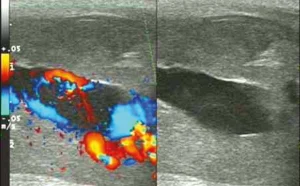

Μετά από εξετάσεις, οι γιατροί παρατήρησαν ότι το πέος του 21χρονου είχε ίχνη ψευδοανευρύσματος, δηλαδή οι φλέβες είχαν τραυματιστεί, με αποτέλεσμα να συγκεντρωθεί μεγάλη ποσότητα αίματος στο πέος. Ο άντρας διαγνώστηκε με μη ισχαιμικό πριαπισμό.